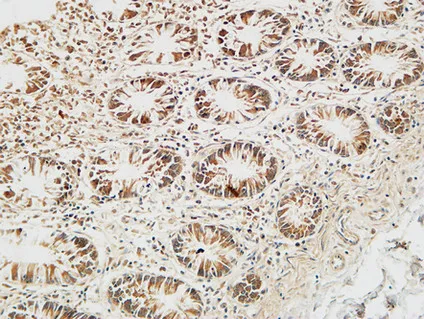

Reg IV Rabbit Polyclonal Antibody

Cat: APRab16998